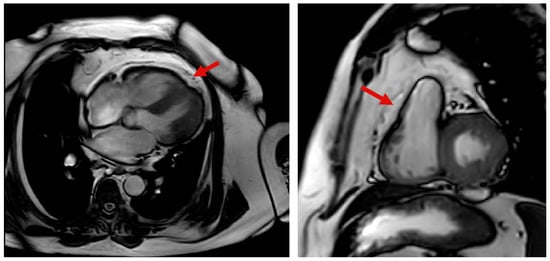

5.2. CMR Evaluation of EAT

- Duca, F.; Mascherbauer, K.; Donà, C.; Koschutnik, M.; Binder, C.; Nitsche, C.; Halavina, K.; Beitzke, D.; Loewe, C.; Bartko, P.; et al. Association of Epicardial Adipose Tissue on Magnetic Resonance Imaging with Cardiovascular Outcomes: Quality over Quantity? Obesity 2024, 32, 1670–1679. [Google Scholar] [CrossRef] [PubMed]

- Malahfji, M.; Al-Mallah, M. Epicardial Adipose Tissue on Cardiac MRI and Cardiovascular Risk: Another Reason to Watch What You “EAT”. Atherosclerosis 2024, 397, 118523. [Google Scholar] [CrossRef]

- Schulz, A.; Gronwald, J.; Hagedorn, C.; Lange, T.; Stiermaier, T.; Evertz, R.; Backhaus, S.; Kowallick, J.; Hasenfuß, G.; Thiele, H.; et al. CMR-Derived Epicardial Adipose Tissue Predicts Risk of Major Adverse Cardiac Events Following Myocardial Infarction Independent of Obesity and LV Function. J. Cardiovasc. Magn. Reson. 2025, 27, 101364. [Google Scholar] [CrossRef]

- Cristobal-Huerta, A.; Torrado-Carvajal, A.; Malpica, N.; Luaces, M.; Hernandez-Tamames, J.A. Automated Quantification of Epicardial Adipose Tissue in Cardiac Magnetic Resonance Imaging. In Proceedings of the 2015 37th Annual International Conference of the IEEE Engineering in Medicine and Biology Society, Milan, Italy, 25–29 August 2015; pp. 7308–7311. [Google Scholar] [CrossRef]

- van Woerden, G.; van Veldhuisen, D.J.; Gorter, T.M.; van Empel, V.P.M.; Hemels, M.E.W.; Hazebroek, E.J.; van Veldhuisen, S.L.; Willems, T.P.; Rienstra, M.; Westenbrink, B.D. Importance of Epicardial Adipose Tissue Localization Using Cardiac Magnetic Resonance Imaging in Patients with Heart Failure with Mid-Range and Preserved Ejection Fraction. Clin. Cardiol. 2021, 44, 987–993. [Google Scholar] [CrossRef]